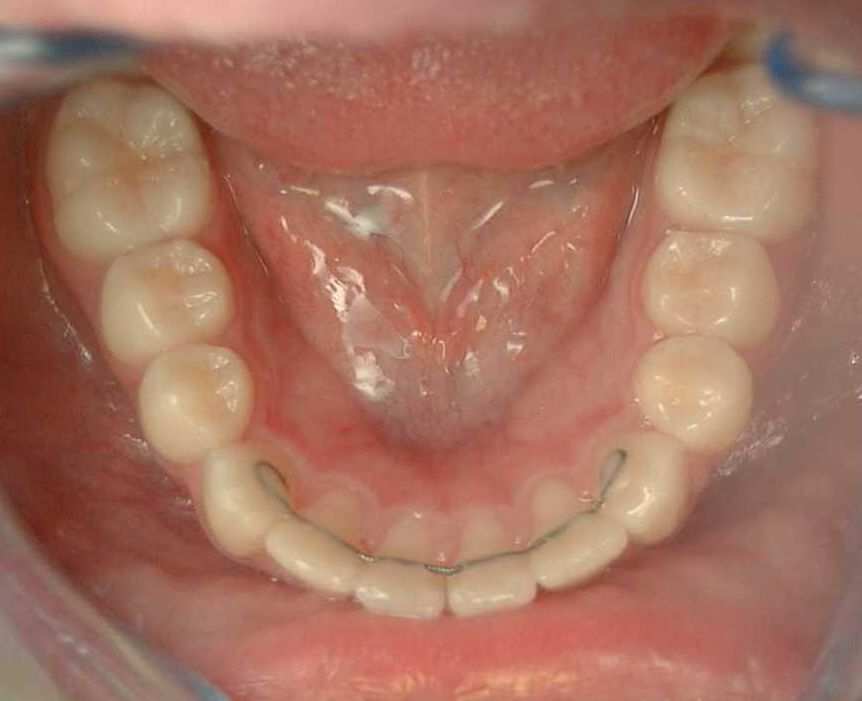

La contention fixe